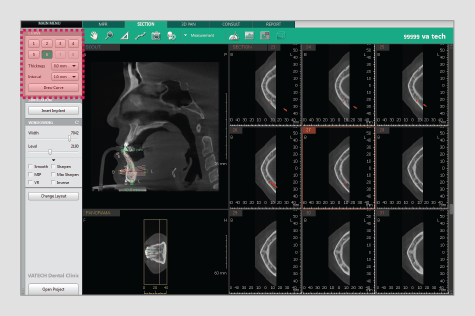

Powered by a new 3D VR graphics engine, the Ez3D-i is the ideal tool to effortlessly obtain the correct perspectives needed for accurate and true-to-measurement diagnosis.

• Intuitive implant simulation tools for collision detection (implant/canal), bone density verification, and oblique viewing tools

• 3 click implant simulation

• Collision detection

• Bone density

• 3D panorama

• Oblique view mode

2-CLICK AIRWAY ANALYSIS

With two clicks, obtain the volume and minimum axial area of

an airway for efficient airway diagnosis.

• Easily navigate and obtain a sectional view by utilizing our new and intuitive 3D panoramic navigation mode

• Simply click and drag our viewing window over the 3D panorama to obtain a sectional view of that region

• Angulation made easy

By clicking 3D Navigator and positioning to ROI,

it’s easy to verify 2D sectional images.

• Available in all viewing modes in the Ez3D-i (MPR/Section/3DPan)

• Colorized bone density viewing modes available

• Adjustable automatic implant collision detection function between multiple implants and/or nerve canal